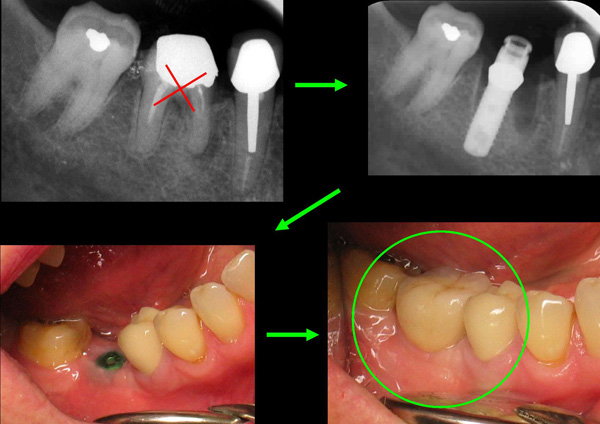

Implant unitaire : remplacement UNE dent (absente ou infectée irrécupérable devant être extraite)